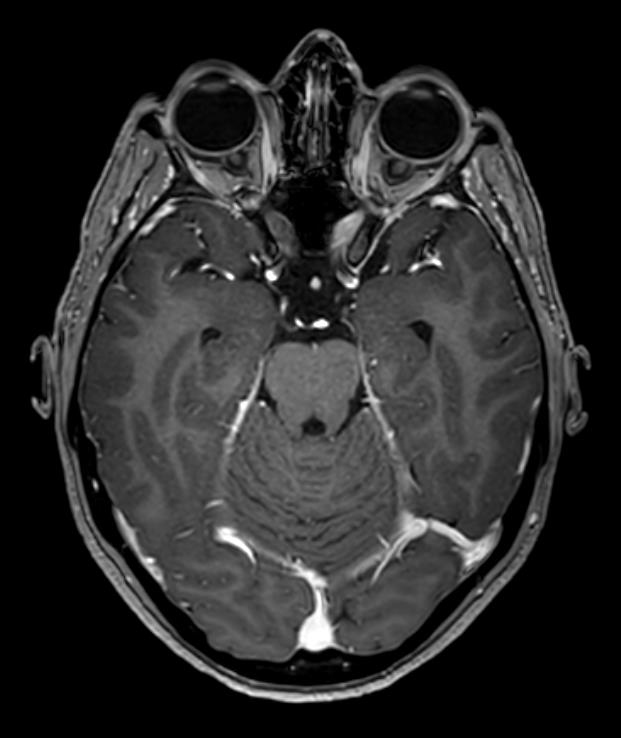

Coupe axiale en séquence T1 : on a une séquence dite anatomique, avec la substance grise qui est grise et la substance blanche qui est blanche (par opposition à la séquence en T2 dite anti-anatomique). Il y a une injection de gadolinium avec rehaussement des sinus veineux. De plus, on peut s’orienter avec une séquence T1, car le liquide cérébro-spinal dans les ventricules latéraux est noir.